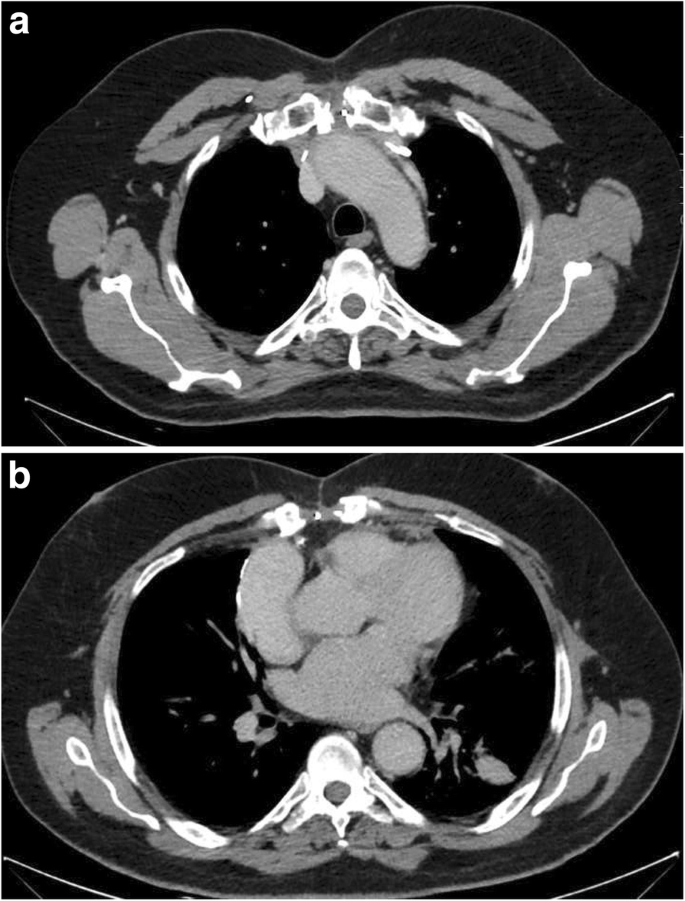

A 57-year-old previously healthy gentleman presented to our service complaining of a new onset shortness of breath for 2 months. He initially sought medical attention outside King Hussein Cancer Center (KHCC) where he was found to have a huge mediastinal mass on a chest x-ray from which a biopsy revealed a thymoma (Fig. 1). At KHCC, a chest computed tomography (CT) scan showed a lobulated anterior mediastinal soft tissue mass measuring 11.3 × 7.7 cm at the level of the aortic arch. It appeared to be inseparable from the anterior wall of the superior vena cava (SVC), compressing it mildly but keeping it patent. In addition, it had a wide area of contact with the ascending aorta and upper pericardium. Multiple small nodular soft tissue masses were seen in the anterior epicardial space, mostly representing small lymph nodes. Otherwise no other mediastinal lymphadenopathy was reported (Fig. 2a, b).

Chest CT scan with contrast, coronal view, mediastinal window showing a lobulated anterior mediastinal soft tissue mass lesion measures 10 X 6 cm (white asterisk) at the level of the aortic arch. The lesion is causing mild compression upon the SVC. However, the SVC is patent. The lesion is inseparable from the anterior wall of the SVC, shows wide area of contact with the ascending aorta, upper pericardium and associated with mild pericardial effusion